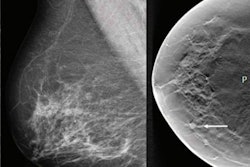

Dense breast tissue is considered a risk factor for breast cancer because it can reduce mammography's sensitivity by masking cancer lesions. It is typically evaluated using the four-point BI-RADS scale, noted a group led by Dr. Veronica Magni of the Università degli Studi di Milano. Women with dense tissue are typically referred for supplemental breast cancer screening via ultrasound or breast MRI.

The group developed and used an algorithm called TRACE4BDensity (DeepTrace Technologies, Milan, Italy) for breast density classification based on convolutional neural networks from mammograms obtained between 2017 and 2020. The algorithm was trained with 760 mediolateral oblique (MLO) images taken in 380 women that were interpreted by seven radiologists; three of these radiologists used a set of 384 MLO images in 197 women to validate the model.